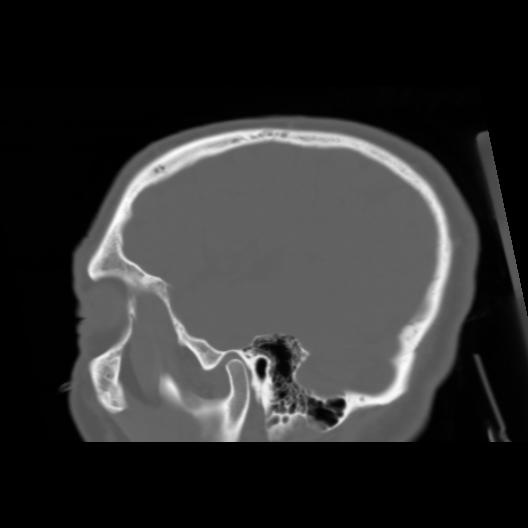

6 CEREBRO,,Sagittal,3.000,CEREBRO,Sagittal,